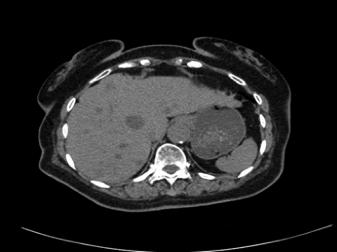

腹部CT平扫:腹部CT肝脏实质内见多发大小不等低密度及稍低密度结节及肿块影,大者位于右肝前上段,大小约3.4cm×2.9cm,部分边界清楚,部分边缘模糊,性质?胆囊未见增大,囊内见沙粒状高密度影,肝内外胆管轻度扩张。十二指肠降段内侧见1.4cm×1.2cm囊状影,其内含气。右肾实质内见囊状低密度影,大小约2.3cm×2.1cm。左侧肾上腺结节状增粗,增生?

2017-1-4